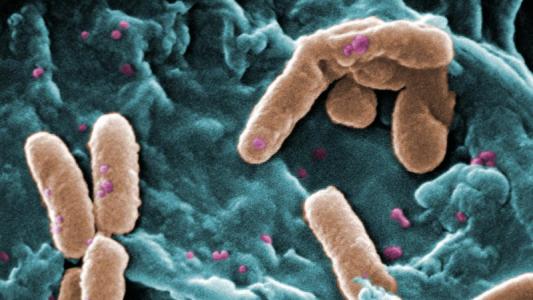

Training the body to fight off drug-resistant bacteria

A new strategy, called host-targeted defense, could help solve antibiotic resistance by upgrading the immune system.

Engineering bacteria in the microbiome could fix previously untreatable genetic disorders.